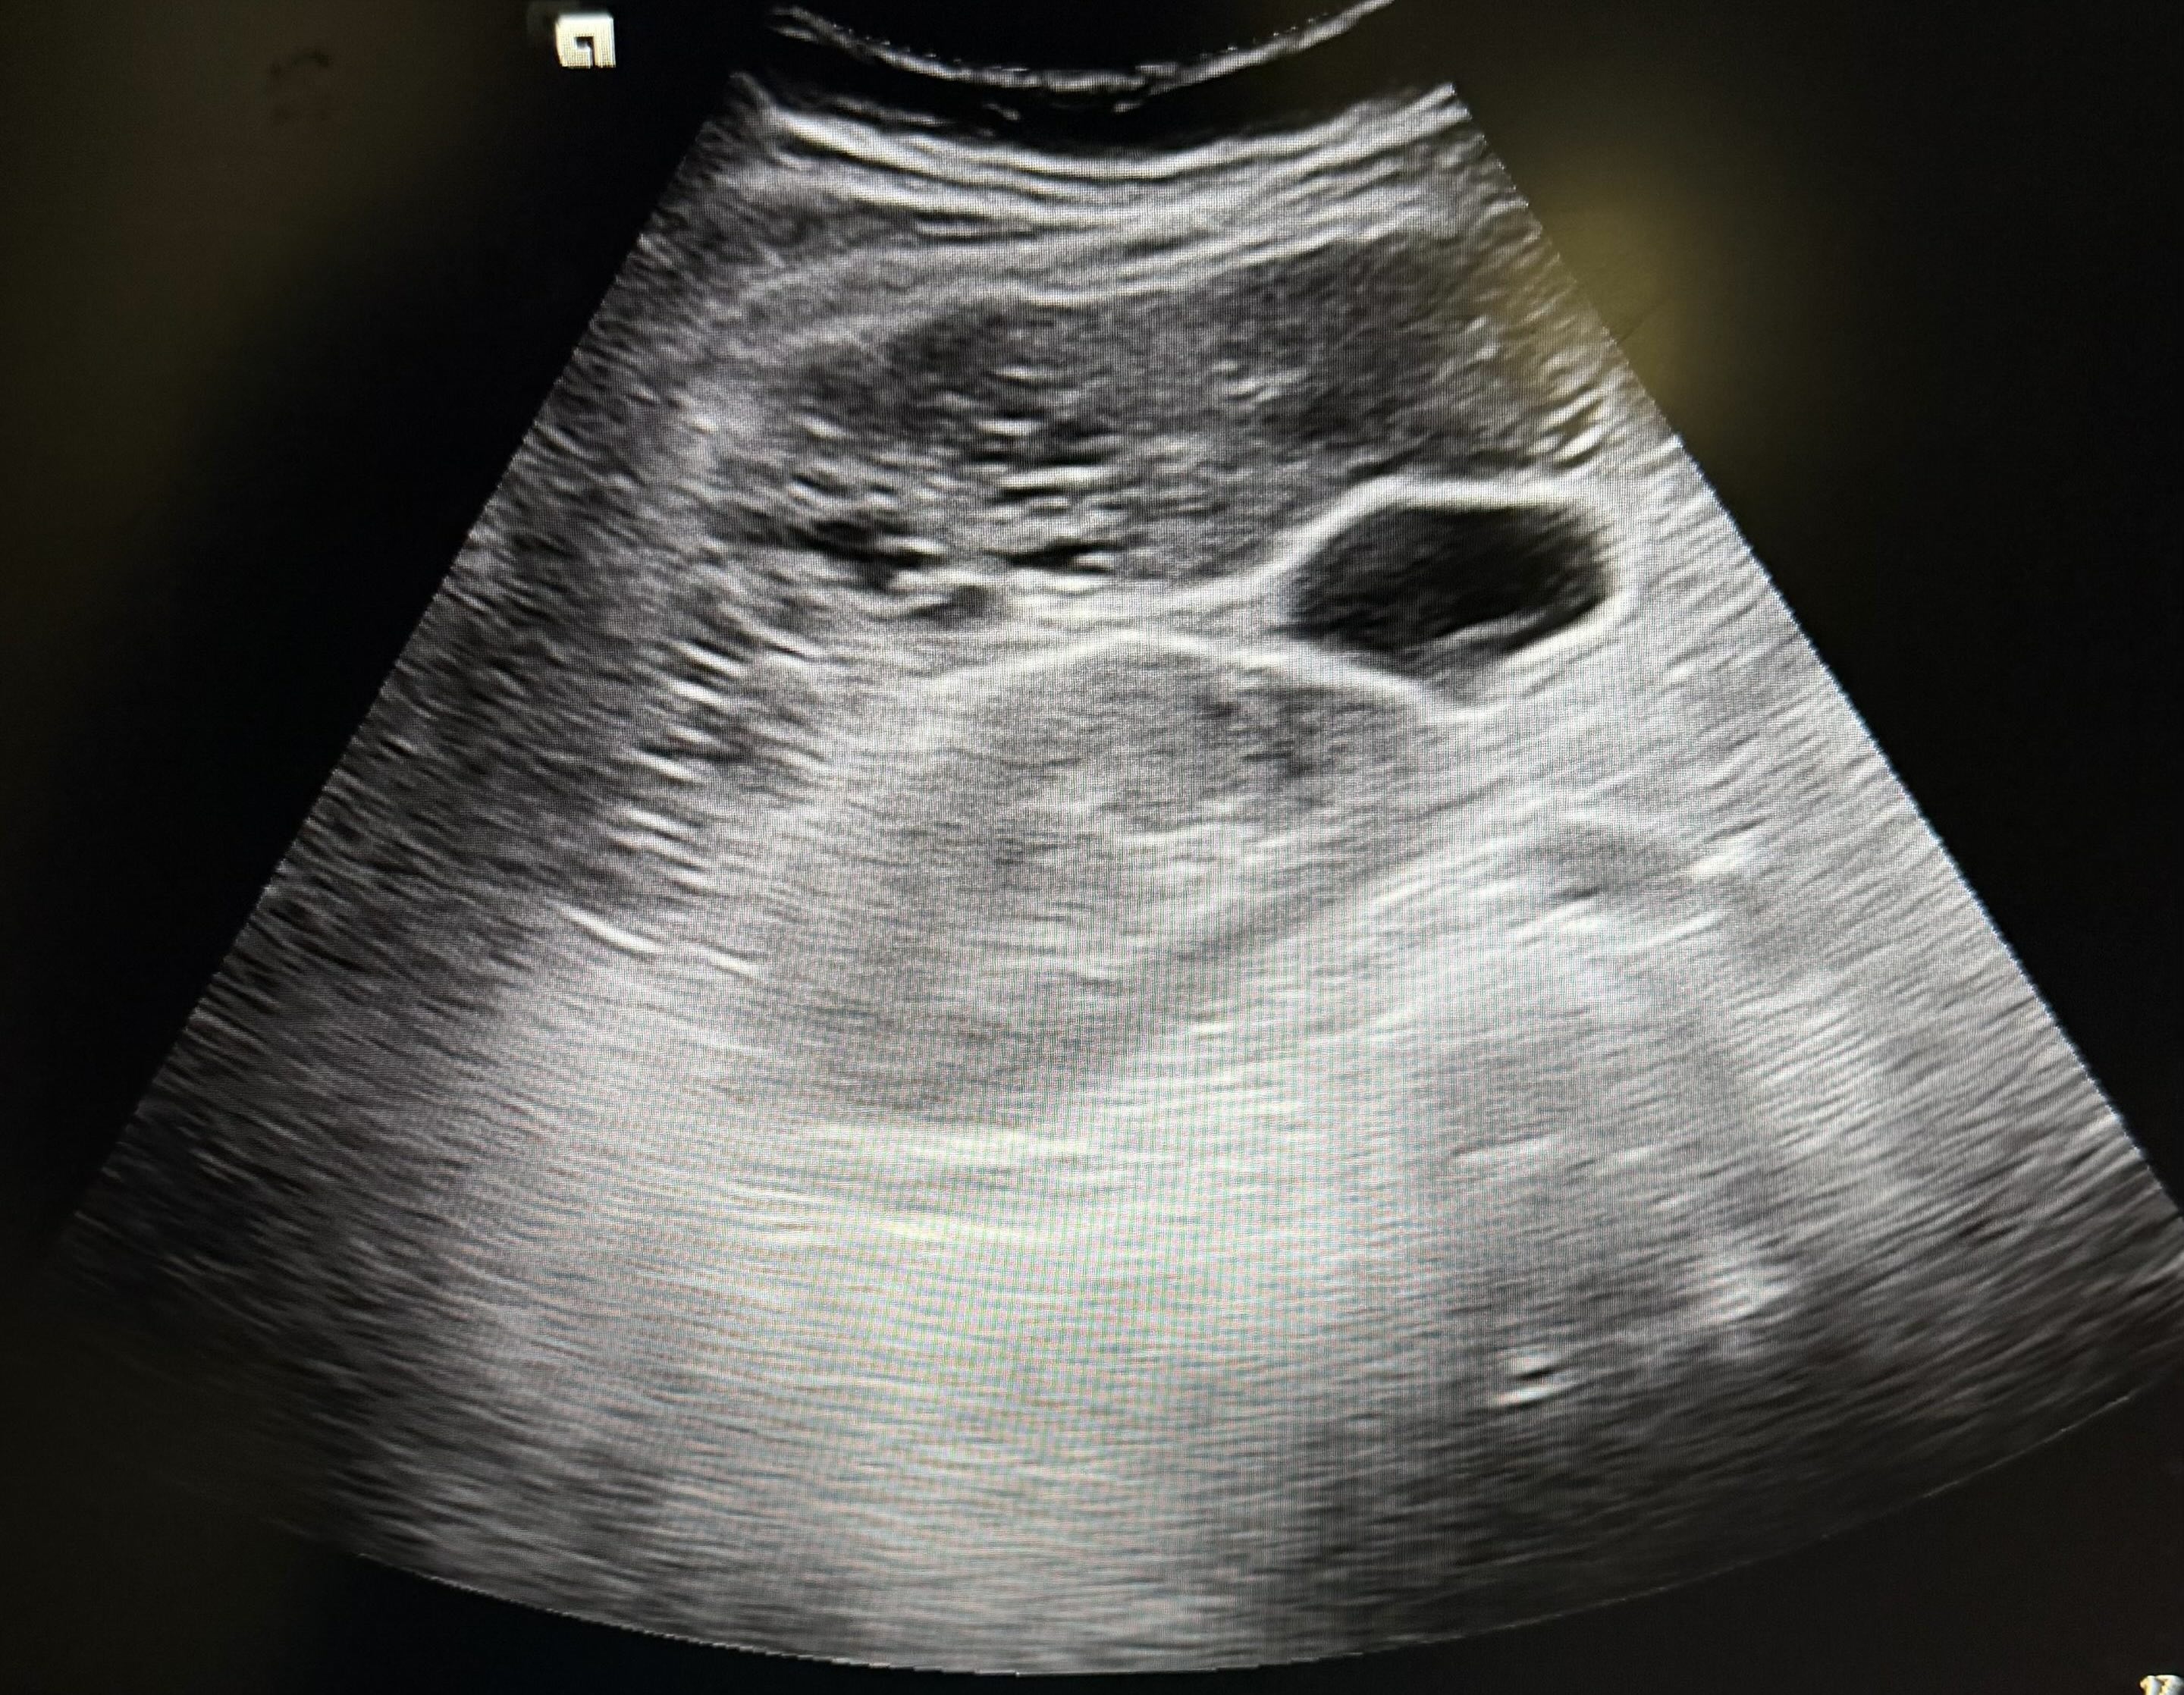

Hallazgos ecográficos

Imágenes quísticas hepáticas múltiples, sugerentes de ser quistes simples hepáticos; debiendo hacer despistaje de enfermedad de Caroli (hamartosis biliar intrahepática).